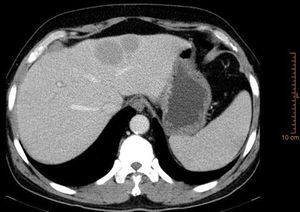

En la TAC aportada se apreciaba una ectasia pieloureteral derecha grado ii/iv, producida por una lesión polipoidea en la pelvis renal que se extendía al uréter proximal, así como lesiones hepáticas (figs. 1-3). La citología urinaria era negativa para células neoplásicas, y la cistoscopia no reveló la presencia de lesión vesical concominante.

Se procede a la punción-biopsia de la zona hepática, con resultado AP de linfoma no Hodgkin de células B (CD20+) (figs. 4 y 5), que se mostró también en la biopsia realizada a posteriori a nivel renal.Posteriormente se procedió a iniciar terapia con rituximab.